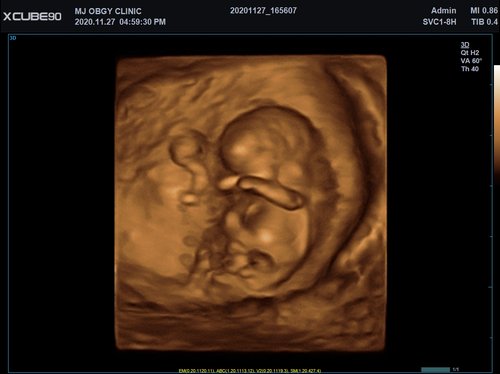

Mit dem X-CUBE 90 beginnt ALPINION eine neue Generation an Farbdopplersystemen, die X- CUBE Serie. Mit Bildverarbeitungstechnologien eines Premiumsystems und neuen Breitband- Schallköpfen mit X + Crystal Signature™ Technologie wartet das neue X-CUBE 90 auf.

Neben der hohen Bildqualität liegt ein weiterer Fokus auf der Vereinfachung und der Anpassung der Bedienung des Ultraschallgeräts. Individuell programmierbare Workflows und ein erweitertes Spektrum an automatisierten Messungen ermöglichen ein schnelleres und genaueres Arbeiten in jeder Situation.

X + Architecture

Die X + Architecture ist eine erstklassige Imaging-Plattform, die durch die Kombination von X + Crystal Signature™, der Schallkopftechnologie mit hoher Sensitivität und Breitbandigkeit, und X + FIT, ALPINIONs modernste Beamforming- und Datenverarbeitungstechnologiengeschaffen wurde. X + FIT ist eine neue Technologie, die den Schallstrahl scharf fokussiert sendet, ein großes Datenvolumen empfängt und mit hoher Geschwindigkeit verarbeitet. Darüber hinaus nutzt X + Crystal Signature™ Einkristalle und unser eigenes entwickeltes Schallkopfmaterial, um eine hervorragende Brillanz zu erzielen und die Diagnosemöglichkeiten zu erweitern.

• SVC1-8H (1-8 MHz) für Ultraschalluntersuchungen in Bereichen Abdomen, Geburtshilfe, Gynäkologie, Urologie, Pädiatrie, EM